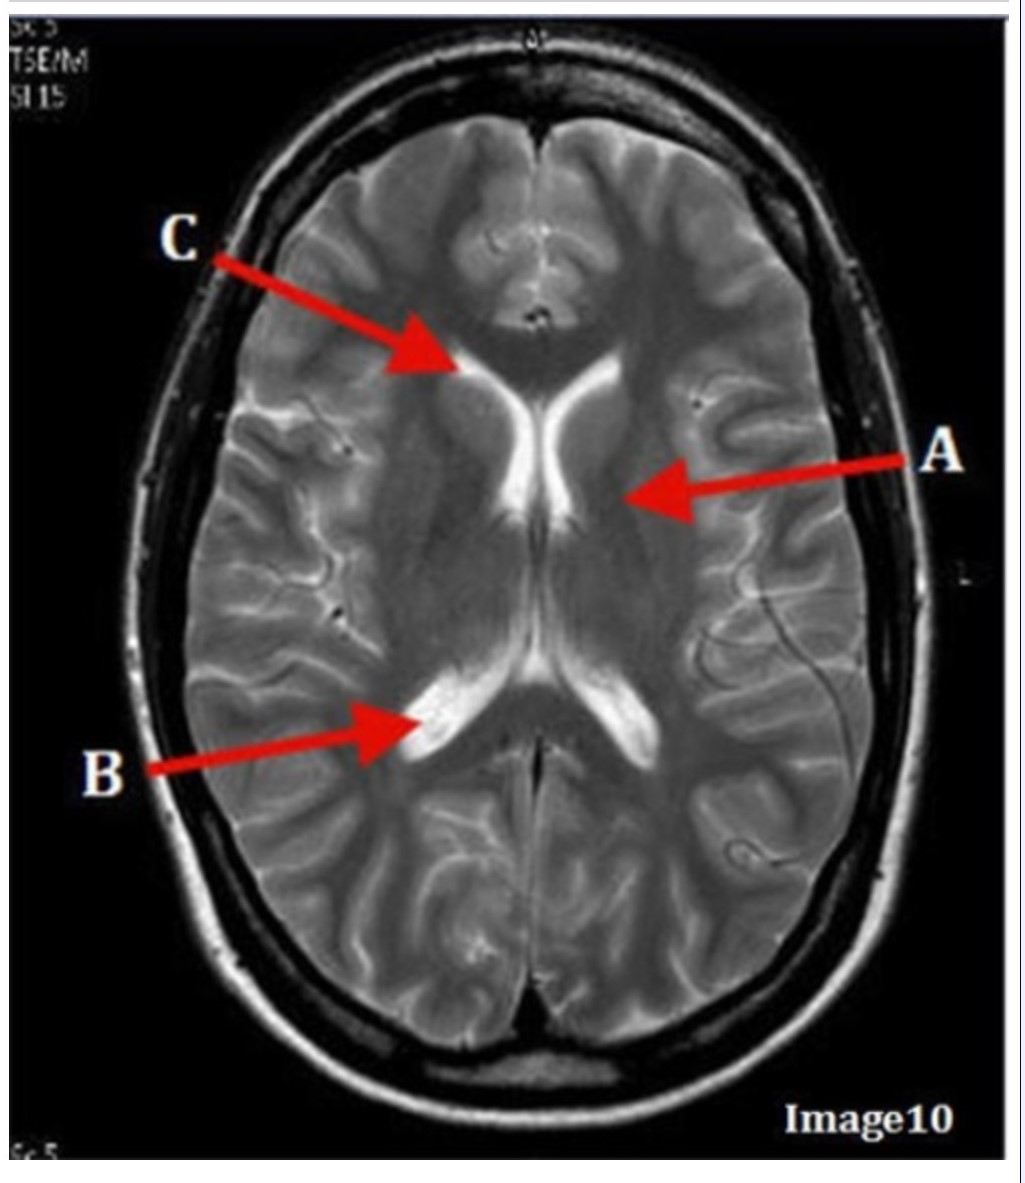

Letter B in Image 10 is pointing to:

A. Third ventricle

B. Basal ganglia

C. Anterior horn lateral ventricle

D. Posterior horn lateral ventricle

Letter C in Image 10 is pointing to:

A. Third ventricle

B. Basal ganglia

C. Anterior horn lateral ventricle

D. Posterior horn lateral ventricle

Letter A in Image 10 is pointing to:

A. Third ventricle

B. Basal ganglia

C. Anterior horn lateral ventricle

D. Posterior horn lateral ventricle

Image 9 is an example of a _____ weighted sequence acquired in the _______ scan plane.

A. T1; Axial

B. T2 FLAIR; Sagittal

C. T2; Axial

D. T2; Coronal